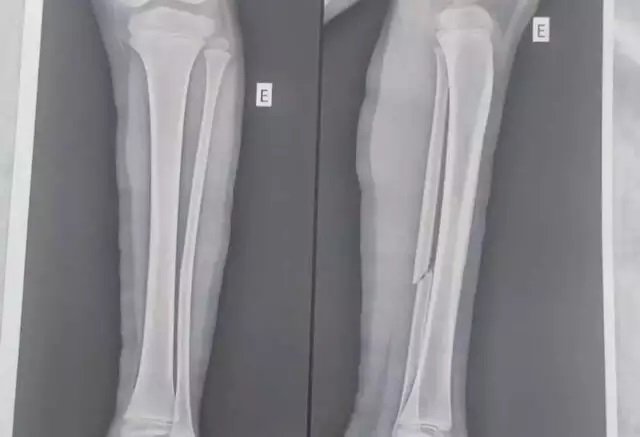

Buscando dia de lazer para família e amigos, a corretora de imóveis Bruna Costa Pereira Lima, de 31 anos, viveu uma saga para conseguir atendimento médico para filha, de sete anos, que quebrou a perna ao ser atingida por uma prancha no balneário Cabeceira do Betione, localizado em Bodoquena. O caso aconteceu no domingo (5).

Quando a menina saía da água, pela escada, acabou atingida por uma prancha de stand up paddle utilizada por outro turista que frequentava o local. Ao procurar ajuda, descobriu que o balneário não possuía salva-vidas, muito menos uma equipe que pudesse ajudar nos primeiros socorros.

“Eles apenas ofereceram gelo para colocar no pezinho dela, mas depois a gente descobriu que era a perna que estava quebrada. O pior para mim foi o balneário não ter um segurança, placas de informações sobre caiaques. É inadmissível um barco no local onde é destinado o trânsito de pessoas e muitas crianças”, disse.

A corretora contou que deixou o local e procurou o hospital de Bodoquena, mas na unidade também houve negligência, onde a equipe médica se recusou a imobilizar a perna da menina, que precisou ser atendida em um hospital de Aquidauana.

“Lá em Aquidauana eles disseram que minha filha não podia ter saído sem a perna imobilizada. Fui chegar em Campo Grande somente às 2h da madrugada de segunda (6), depois de toda saga”, relatou.